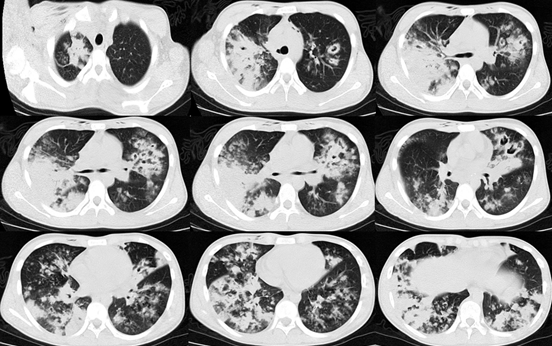

辅助检查:起病1周左右(20181月8日)外院胸部CT出现了明显的纵隔气肿,沿支气管血管束分布的多发结节和斑片影。

图片

转入我科当天行胸部CT检查,距出现症状已2周余,与前相比进展快速,出现大片实变影,原有结节已融合,并且出现空洞。

IAA的影像学特征具有提示意义,其影像学一般是在磨玻璃影背景上新发的结节和斑片影,病变特点是沿着支气管血管束分布,而典型的空洞和新月征不多见。

大片实变影也相对特异,且提示预后差!